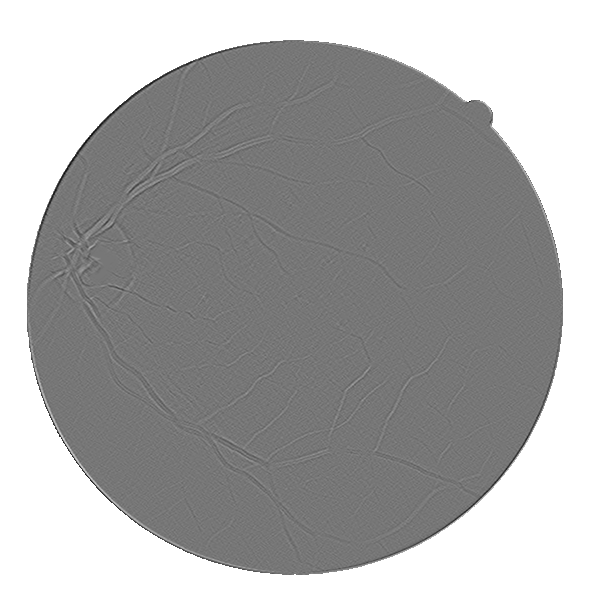

4.2 Validation of the Stationary Wavelet Transform

Having analyzed our Base System, we evaluate the effects of incorporating the SWT into it. The results of each variant are shown in Table 4, while the probabilistic predictions can be seen in Fig. 5. The patches coming from the SWT were concatenated in the input, by varying the total number of input channels. We resorted only to detail coefficients since the goal was to enhance image transitions. We started by concatenating the detail coefficients of the first level in the initial green channel input – BS + . Then, we added those of the second level – BS + + . Finally, only the latter were kept – BS + .

Analyzing the results of the tests performed, we notice that all the alternative strategies improved the performance of the Base System, in terms of Acc and AUC. This means that the use of features based on the wavelet decomposition, whose effectiveness for vessel segmentation is well-known (Soares et al.,, 2006; Zhang et al.,, 2017), is also beneficial when combined with a deep learning methodology. In particular, we see that the first level SWT coefficients used on BS + were less effective than those of the second level applied on BS + . The first level translates spectral information of higher frequencies; this seems to have induced more false positives, as can be seen in Fig. 5. On the other hand, the second level SWT coefficients introduced statistically significant differences to the Base System, in both Acc and AUC, which seems to reinforce the idea that even deep learning methods can benefit from domain knowledge. In fact, they allowed to reduce the combination of false positives and false negatives as we can see in Fig. 5 as well. From now on, we will refer to the best model (BS + ) as Proposed.